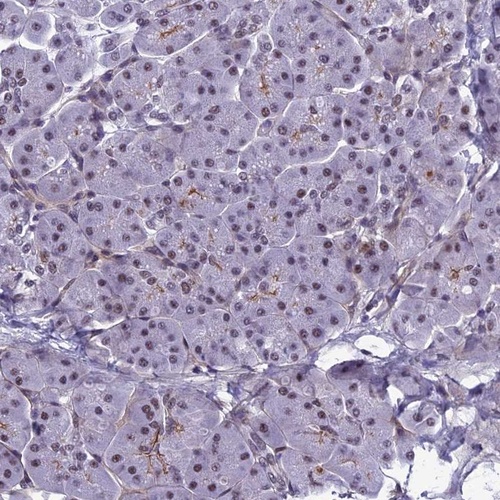

Immunohistochemistry analysis in human cerebral cortex and pancreas tissues using Anti-RSRC1 antibody. Corresponding RSRC1 RNA-seq data are presented for the same tissues.